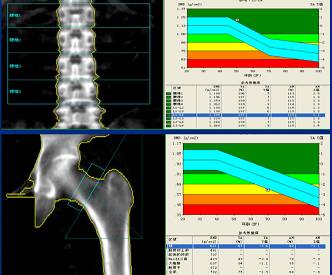

骨质疏松症是以骨量降低,骨组织显微结构发生退变,导致骨脆性增加,骨强度下降

骨密度测定对于各种原因所致骨质疏松症,灵敏度高,诊断率高。骨密度测定有助于协助诊断骨质疏松症。

通过骨密度检测,监测老年骨质变化,及时进行预防性治疗,控制骨质疏松症的发展速度,降低骨质疏松症并发症的发生率具有重要意义